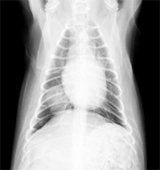

主訴:1ヶ月前からたびたび咳が認められ、回数が増えてきたために近医を受診、肺のレントゲン検査にて、右肺後葉に腫瘍を疑う陰があるとのことで当病院にご紹介で来院されました。

レントゲンにて右肺後葉に腫瘍性病変を確認、咳に原因は腫瘍によるものと判断し、腫瘍を含む右肺後葉の全摘出手術を行いました。

腫瘍は右肺後葉の中央部にあり、他の肺葉には転移はなさそうでした。通常通り肺葉切除を行い、腫瘍を完全切除しました。

摘出した肺腫瘍です。

術後は2日目には食欲も改善、3日目には集中治療室(ICU室)から出ることができ、術後8日目に退院としました。病理組織検査では肺乳頭状腺癌との診断でした。術後1ヶ月目から補助的化学療法(抗がん治療)を3ヶ月間行い、幸い1年経過した今でも再発なく元気で暮らしています。肺などの内部臓器の腫瘍は発見が遅くなりやすく、手術自体できない症例も実際にいるため、日頃からの健康診断や少しの異常もしっかりチェックしていく必要があると感じました。